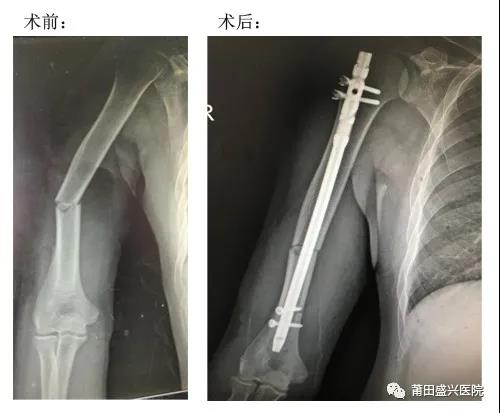

近日,我院骨科成功開展兩例微創(chuàng)治療肱骨中段骨折手術(shù),患者術(shù)后恢復(fù)良好,均已順利出院……